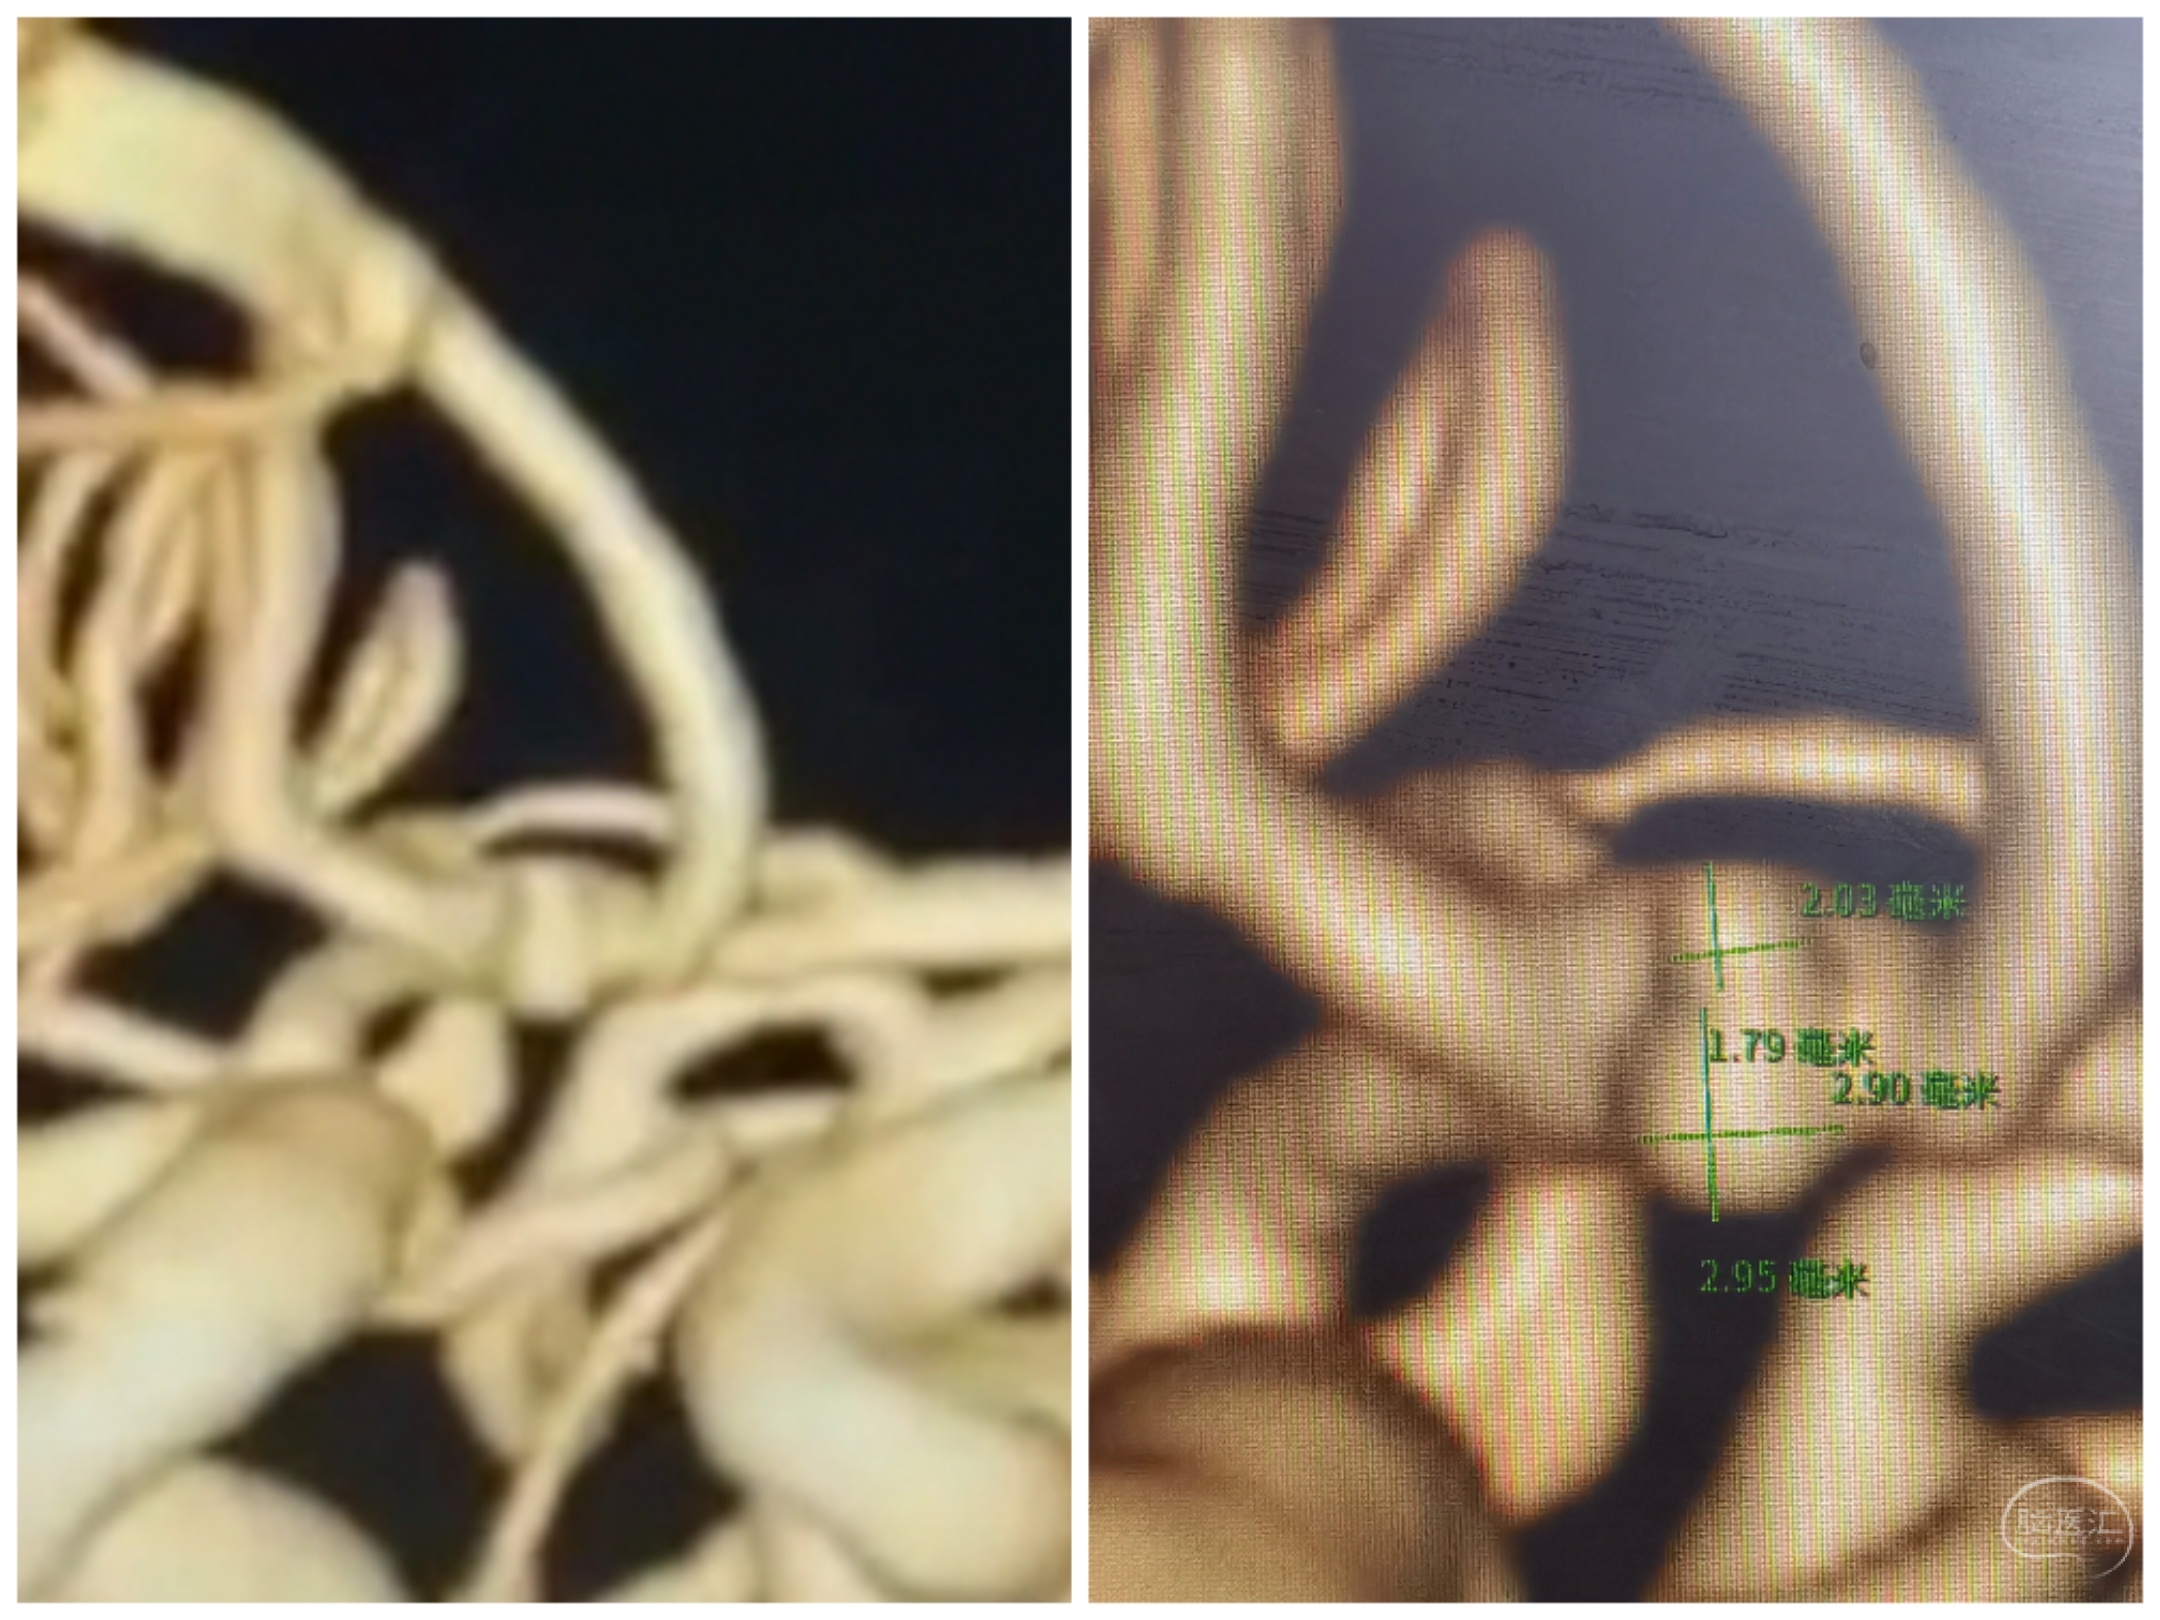

术前CTA,前交通动脉瘤,双侧A1独立

术前CTA情况

3D重建